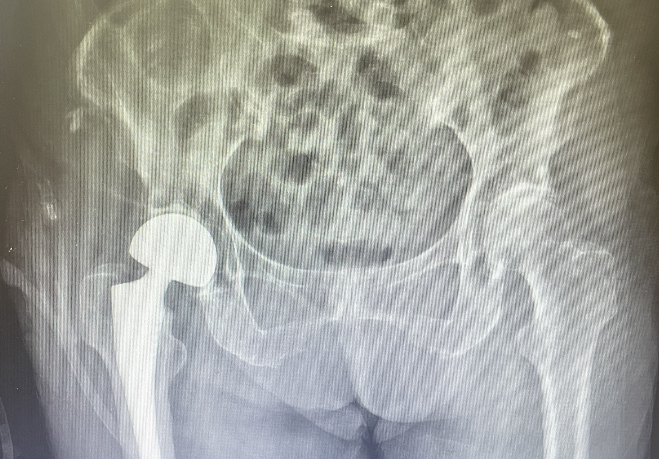

手术当日,在麻醉科、内科、骨科医疗团队的共同努力下,陈上卫、徐光辉医师团队为张奶奶行右侧人工股骨头置换术,术中严密监测血压减少术中出血量。手术历时40分钟,顺利完成。术后复查X光片,人工髋关节位置良好,术后第一天即可下床站立,并在助行器辅助下行走。康复科孙秀珍副主任医师为张奶奶制定术后康复方案,在出院前,再次告知术后康复的重要性,以及预防再次跌倒的措施。